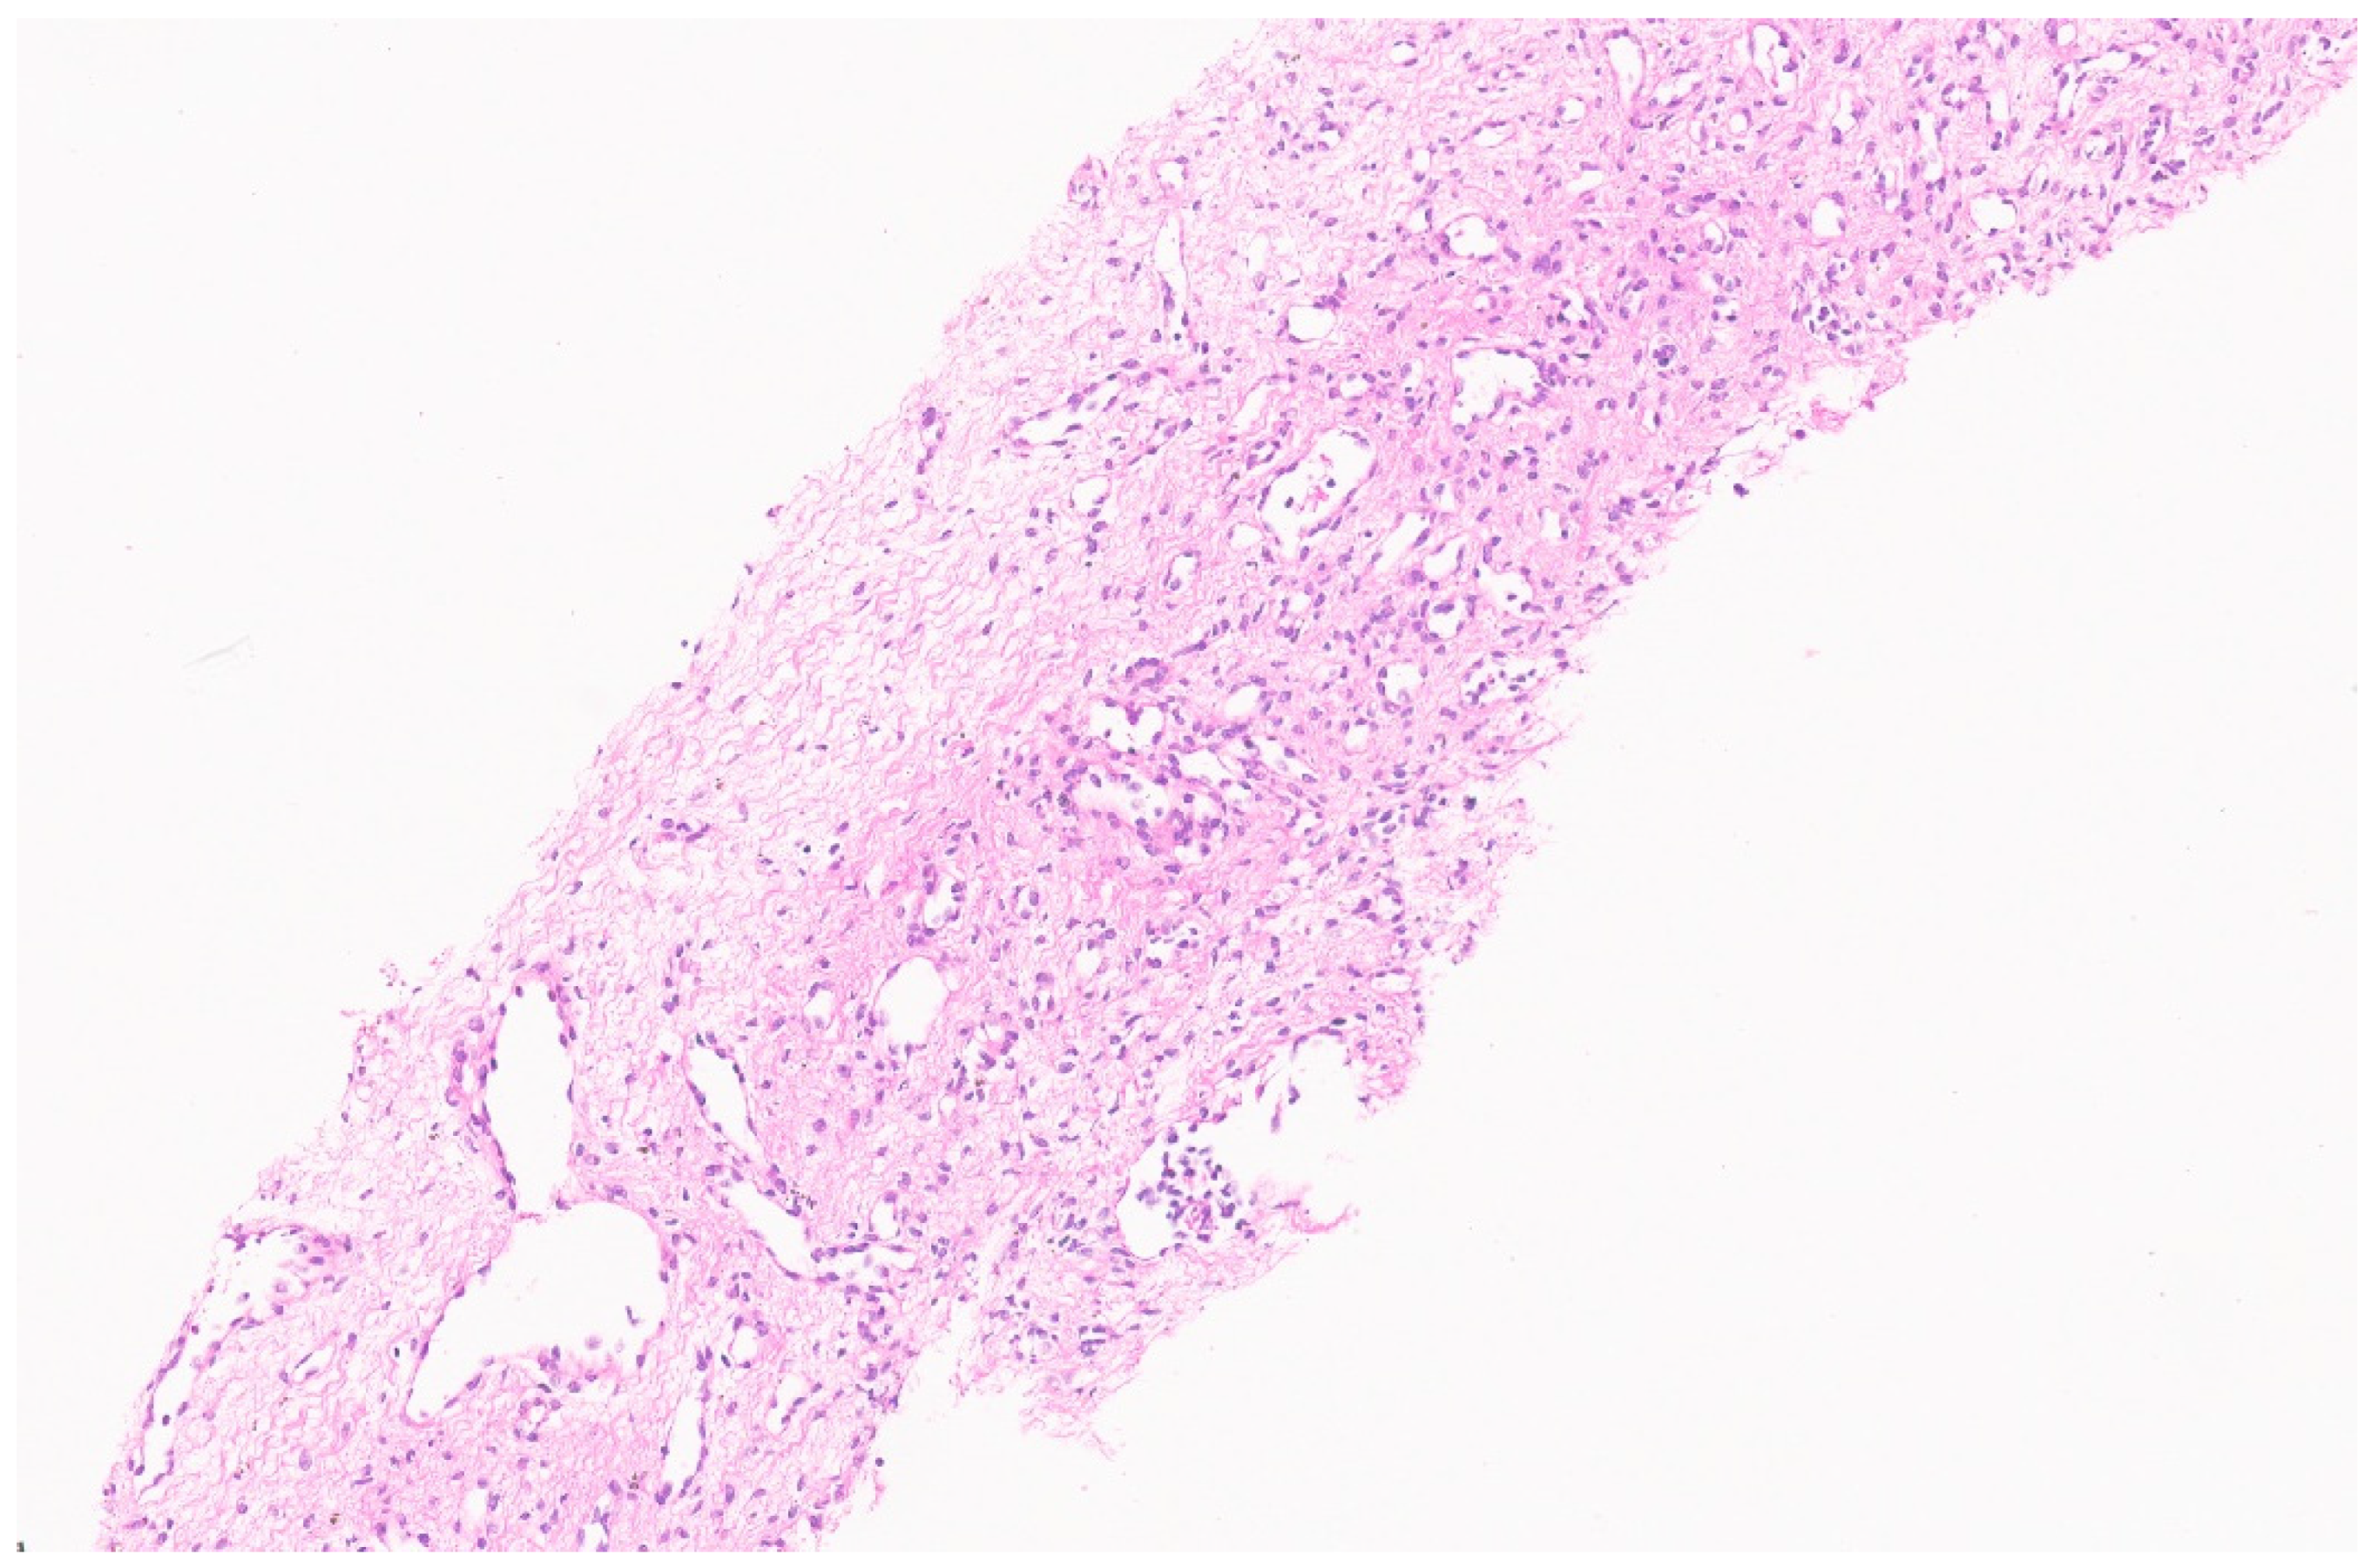

6.3. Pathology

10.3. Pathology